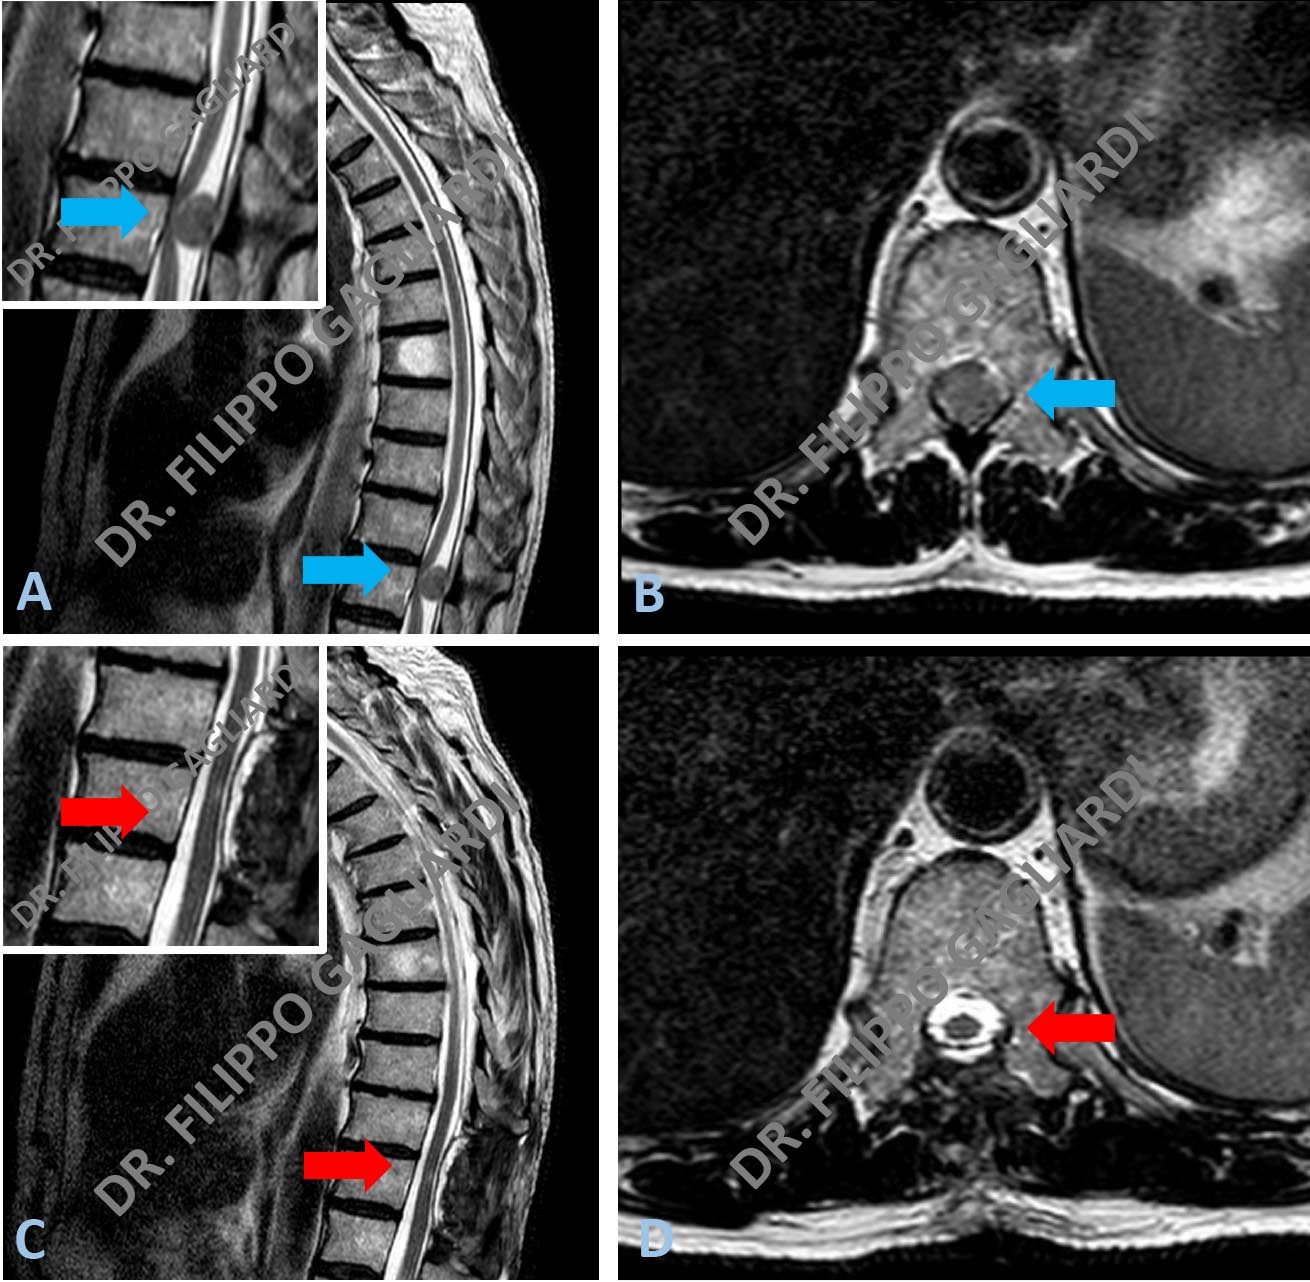

meningioma dorsale Caso di meningioma dorsale. Il tumore disloca in avanti e comprime il midollo spinale (frecce azzurre Figura A e B). Il Paziente è stato sottoposto ad intervento di laminectomia (apertura del canale vertebrale) ed asportazione del meningioma. La RM di controllo post operatoria documenta l’asportazione totale della massa e la conseguente decompressione del midollo spinale (frecce rosse Figure C e D).

Ernia discale lombare Caso di ernia discale lombare L4-L5 (frecce azzure Figure A e B). ). Il Paziente è stato sottoposto ad intervento di erniectomia. La RM di controllo post operatoria documenta l’asportazione totale dell’ernia e la conseguente decompressione delle radici nervose (frecce rosse Figure C e D).